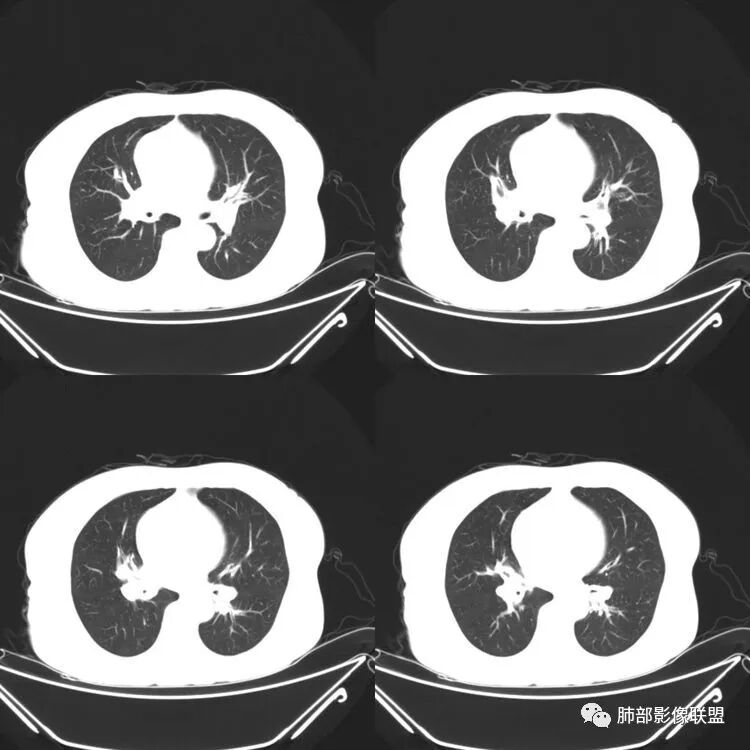

患者,女,64岁,反复咳嗽、咳痰、胸闷10年,加重2周。气管支气管及两肺下叶 支气管弥漫性的环状增厚,管腔扩张,管腔感觉比较松弛。第一感觉,气管支气管淀粉样变。鉴别诊断,1、支气管内膜结核,肺内散在一些支气管的播散病灶,粟粒结节为主,形态比较单一。2、复发性的多软骨炎,就得了解一下其他部位,有没有多个部位的软骨炎。这个病人右侧胸廓缩小,升主动脉明显的扩张,其横径明显的超过了降主动脉。

南边:肺部有肺气肿支气管腔狭窄淀粉样变性?复发性多软骨炎?血管炎?慢支?结核?曲霉菌?南边:一般还是淀粉样变性与复发性多软骨炎鉴别其次就是支气管骨化症,但是骨化下朝上,且壁结节状钙化明显,本例不太支持。至于结核、曲霉菌?1.结核,一般不会这么广泛,支气管壁狭窄后扩张2.曲霉菌可以这么广泛,但是支气管壁管腔扩张,而且附近脂肪间隙有炎性反应,不太支持;3.血管炎,一般合并肺内有病灶,但是声带受累,放待排;4.软骨炎一般全身受累,例如耳廓等;而且膜部不受累,不太支持;倾向于淀粉样变性;淀粉分很多型,气管支气管是最常见的。尘缘:影像上生理性钙化与支气管骨化无法区别,镜检也不好鉴别,需要依赖活检,看粘膜中是否合并炎性改变(淋巴细胞,组织细胞等炎性细胞侵润)来鉴别Coke with ice:经常看到的这种是老年性肺改变,又称年龄相关肺改变。气管和支气管弥漫性软骨钙化,常见老年女性。尘缘:支气管骨化症很罕见的,所以绝大多数还是生理性钙化。对于老年人,无临床症状的钙化,还是基本上都是生理性钙化,无临床意义。大雄:如果管壁钙化伴明显增厚 影像还是提示一下建议支气管镜稳妥些